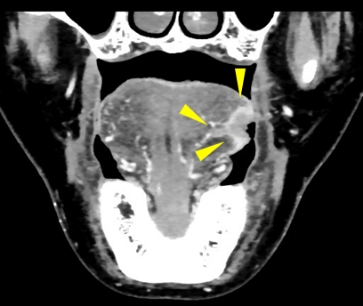

一般的に舌がんの術前の画像診断ではMRIが有用とされており、腫瘍のサイズや深さの評価が行われます。CTを使った従来の撮影方法では、歯科金属の影響でうまく腫瘍を描出することができませんでした。我々は超高精細CT(図1)を用い撮像の方法を工夫することで、舌がんをできるだけ正確に測定する試みを行っています。そうすることで非常に細かい、いわゆるキレイな画像を作成することができ、腫瘍の境界を鮮明に描出し、腫瘍のサイズをより正確に測定することが可能になりました(図2)